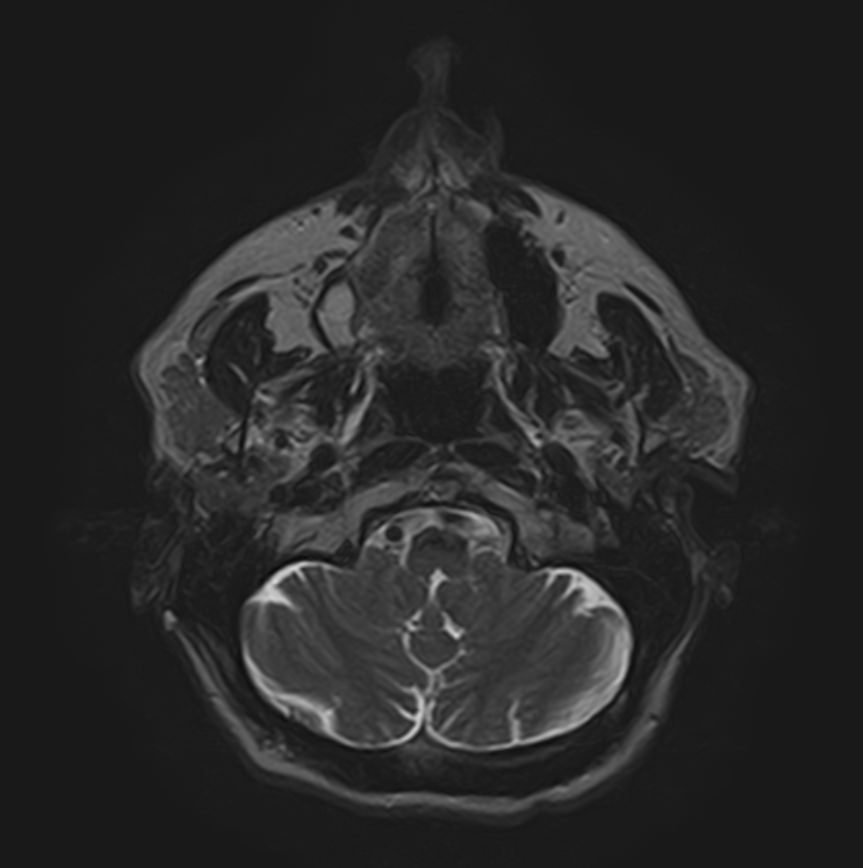

Магнитно-резонансная томография мягких тканей широко используется для детальной визуализации мягкотканных структур.

С помощью МРТ можно оценить состояние мышц, фасций, межфасциальных пространств, синовиальных оболочек, связок, сухожилий, сосудисто-нервных пучков, лимфоузлов и лимфатических протоков, надкостницы, кожи, подкожно-жировой клетчатки.

- Нейропатии различного генеза (посттравматические, на фоне эндокринных заболеваний, аутоиммунных заболеваний, злокачественных новообразований).

- Воспалительные поражения нервов и нервных сплетений (шейного, плечевого, поясничного, крестцового).